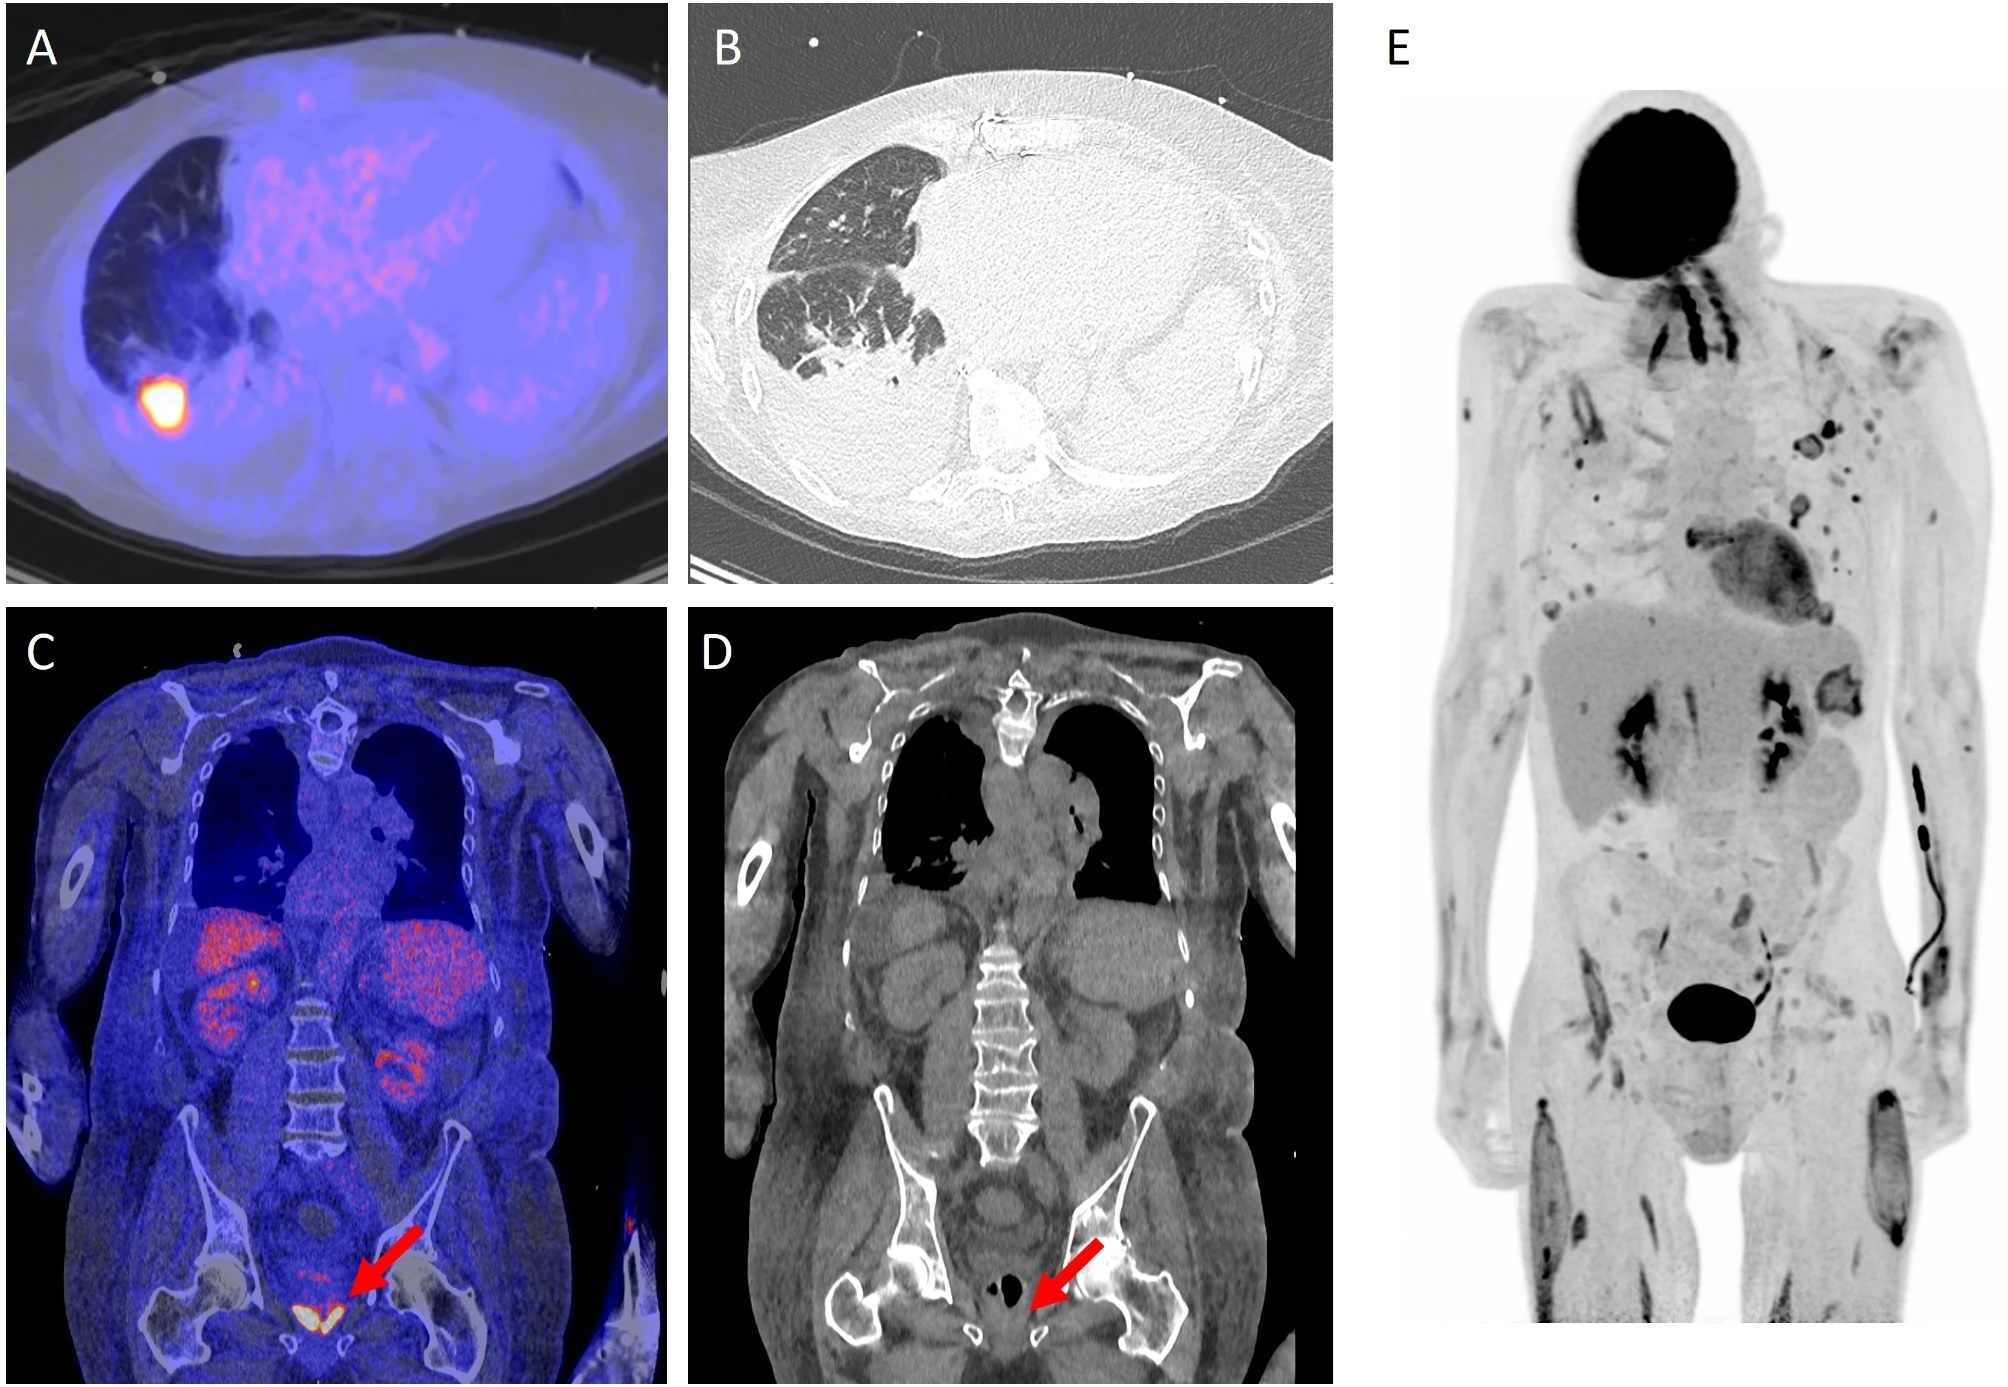

41-year-old man. (A.) CT Chest axial: peribronchovascular lesions within the superior segment of the left upper lobe. (B.) MR C Spine sagittal T1 contrast fat sat: round lesion at the level of C3 with peripheral hyperintensity. (C.) MR C Spine sagittal T2: thick-walled lesion at the level of C3 within the cervical spine with central hyperintensity. (D.) MR Brain axial T2: small lesion of the left frontal lobe that is hyperintense with leptomeningeal enhancement. There is also associated mild cortical edema.